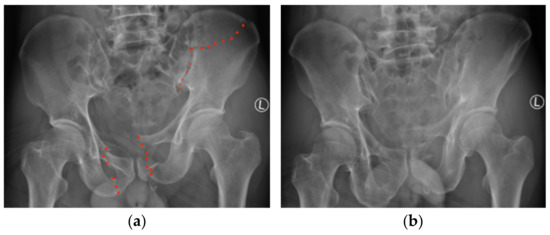

2. Case Report